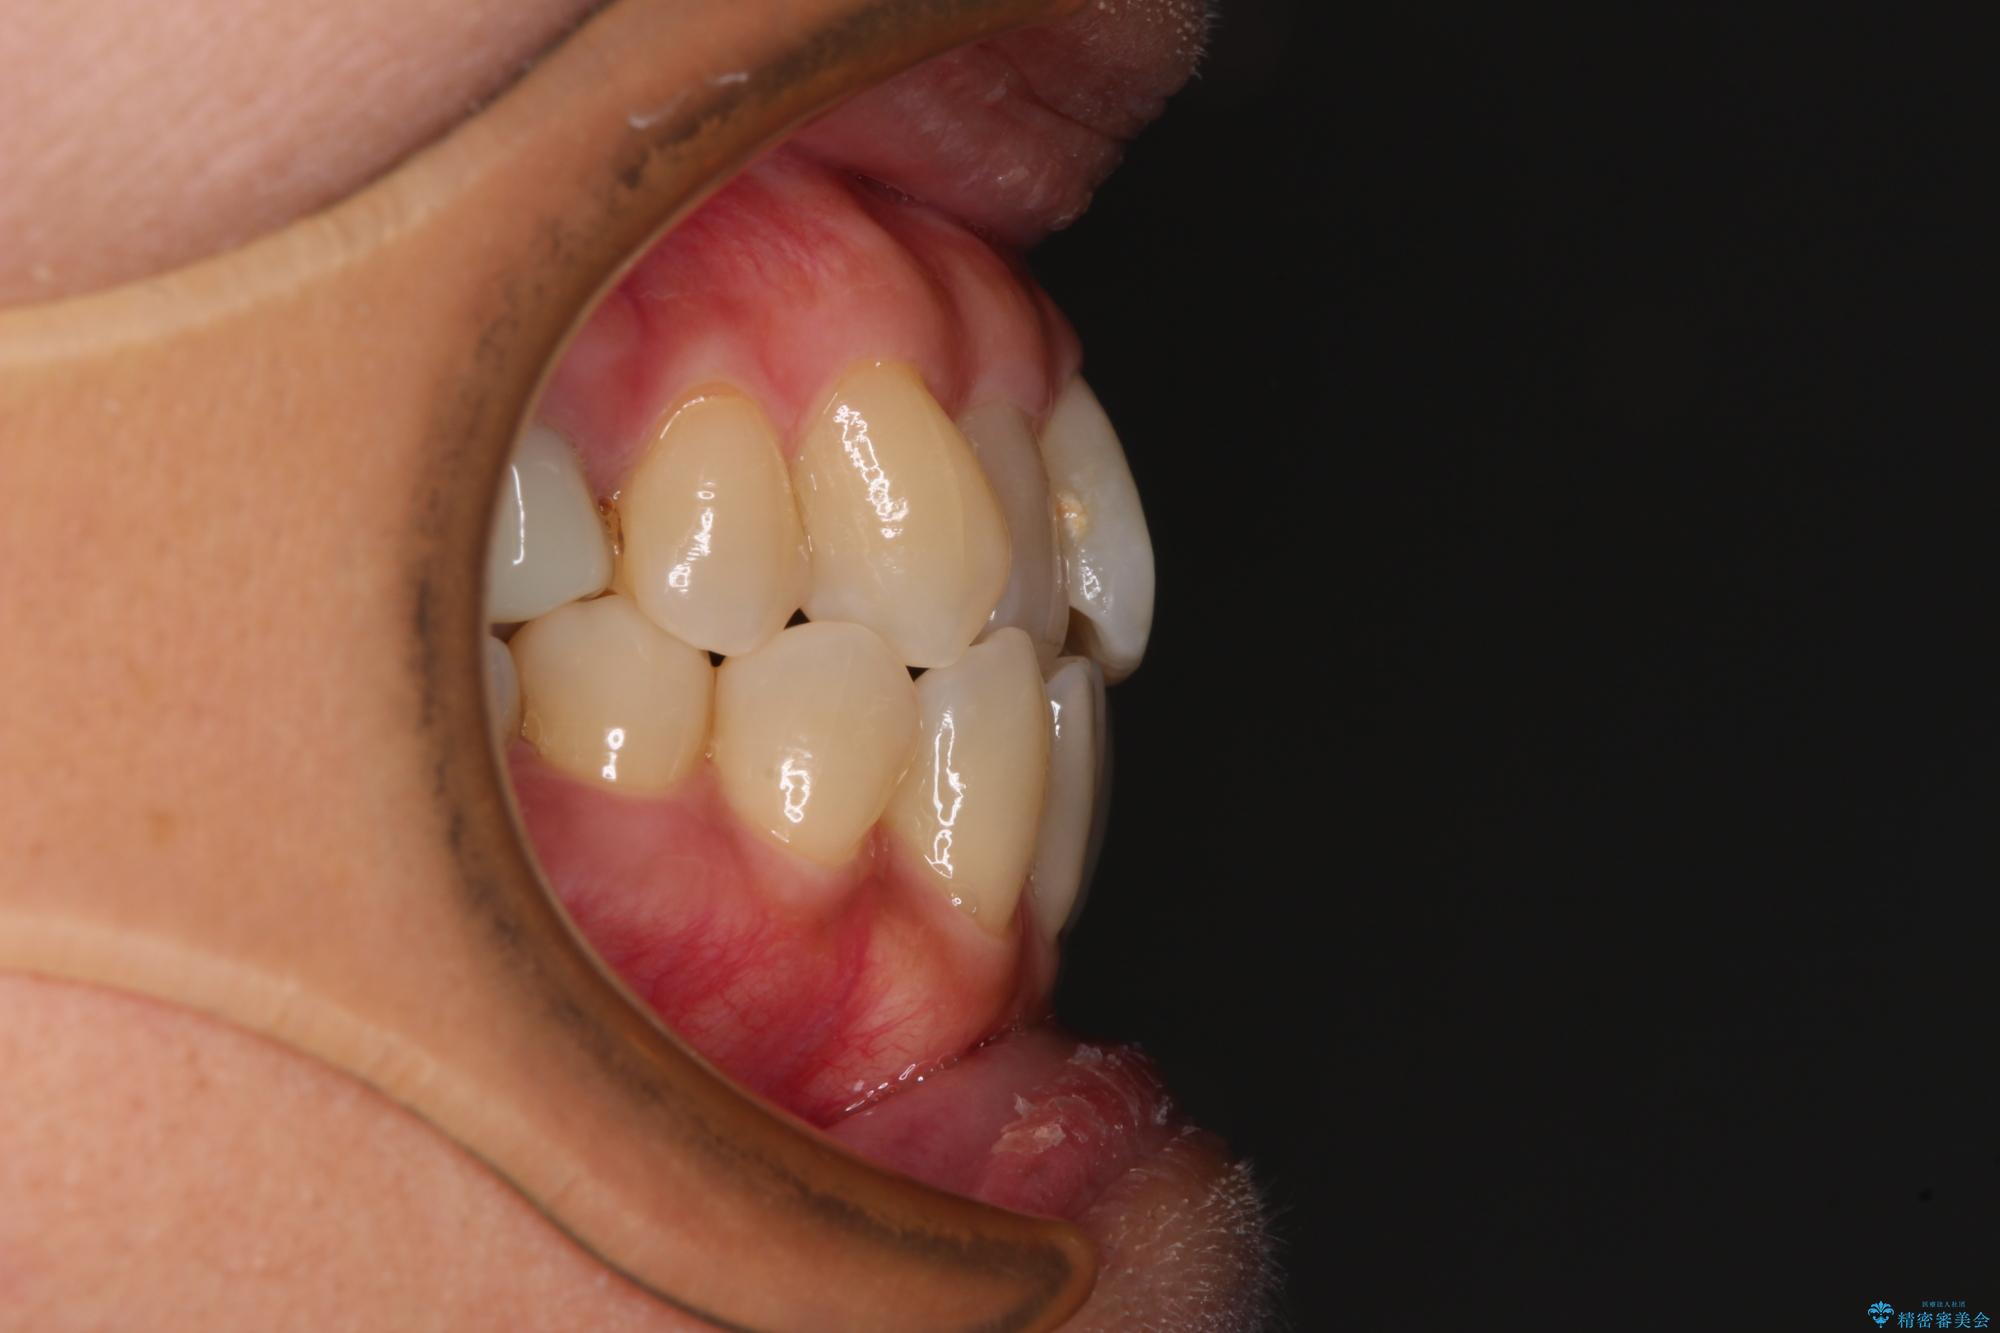

- 前歯のデコボコや八重歯を治したいとのことで来院された患者様です。

受け口傾向の骨格であり、前歯はクロスバイトまたは切端咬合となっており、下顎を中心に歯列全体の後方移動を行い、IPR(歯と歯の間を削る)によってデコボコが解消するように設計し、インビザラインにより治療を行うこととしました。

受け口傾向のインビザライン矯正は比較的治療を行いやすいため、きれいに仕上げることができました。舌の突出癖が顕著であったため、改善のためのトレーニングをしっかりと行っていただきました。